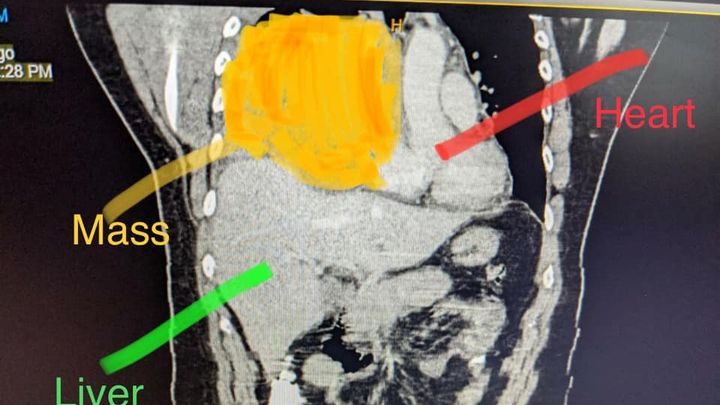

Out of the blue I was diagnosed with pneumonia and a couple weeks later with a mass in my chest- which turned out to be a Germ-Cell Tumor of Testicular Cancer

(extremely rare)

The results from the two MRIs they did yesterday came back. The one for my brain is great but the one for my spine does show that there is infiltration on the T3 vertebrae. That means there is a very small tumor in my spine that's the same type as the one that's in my chest.